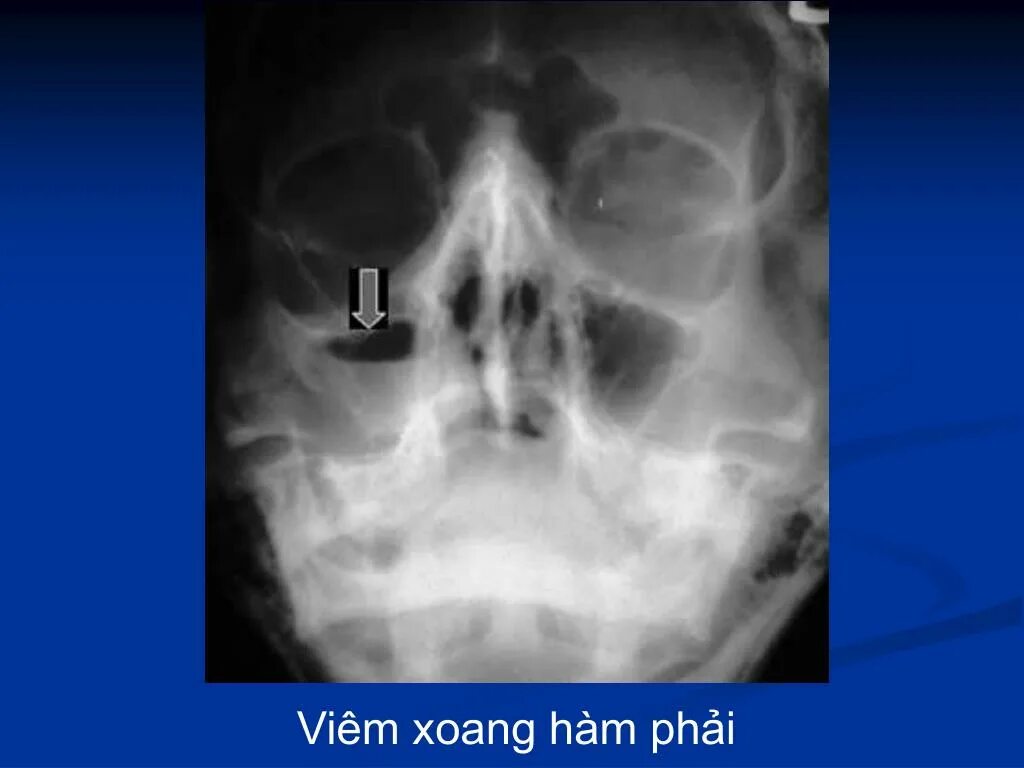

Сфеноидит симптомы